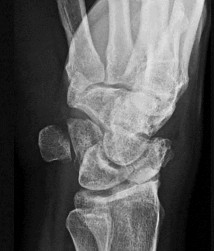

A 30-year-old male sustains an axial load to a plantarflexed foot. On physical examination, there is pronounced plantar ecchymosis and localized pain with passive pronation and abduction of the forefoot.

The primary stabilizing ligament of the disrupted joint complex connects which two osseous structures?

Explanation

Plantar ecchymosis in the midfoot is the pathognomonic sign of a Lisfranc injury. The Lisfranc ligament is an interosseous ligament that represents the strongest and most critical stabilizer of the tarsometatarsal complex. It runs obliquely from the lateral aspect of the medial cuneiform to the medial base of the second metatarsal. There is notably no direct transverse ligamentous connection between the bases of the first and second metatarsals.